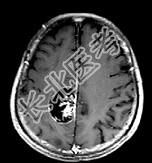

- 单项选择题男,68岁, 头痛头昏、左侧肢体肌力减退3个月余,请根据所提供图像, 选择最可能的诊断是 ( )

A、(右顶叶镰旁)血管外皮瘤

B、(右顶叶镰旁)转移瘤

C、(右顶叶镰旁)脑膜瘤(血管瘤型)

D、(右顶叶镰旁)胶质瘤

E、(右顶叶镰旁)恶性脑膜瘤